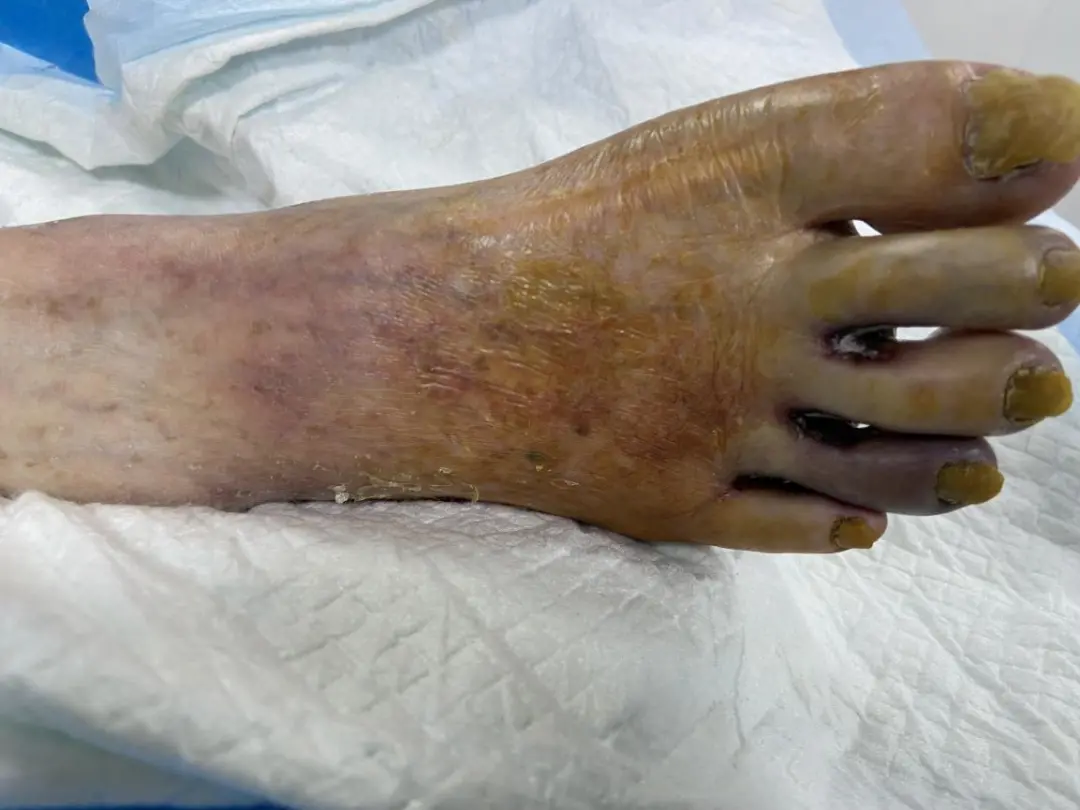

近期,我院接诊了一位75岁的阿婆。她双下肢发凉多年,但没有重视起来。近来,最近1个月出现了脚趾头反复出现伤口—愈合—出现伤口,才选择就诊。经检查发现,阿婆的下肢动脉发生了严重的闭塞。

脚趾发黑、发凉?要警惕下肢动脉硬化闭塞、糖尿病足!

总之,下肢动脉硬化闭塞和糖尿病足都会由于血管狭窄或闭塞,导致血流缓慢或者不通,最终引发脚趾缺血坏死。

以开头的阿婆为例,就是通过微创介入手术,用导丝开通她的足背血管,直通脚趾,恢复了阿婆的下肢血供。